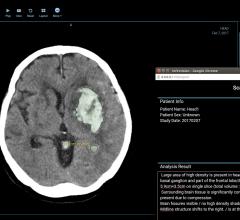

February 21, 2020 — Glioblastoma is an aggressive, killer disease. While victims of this fast-moving brain tumor ...